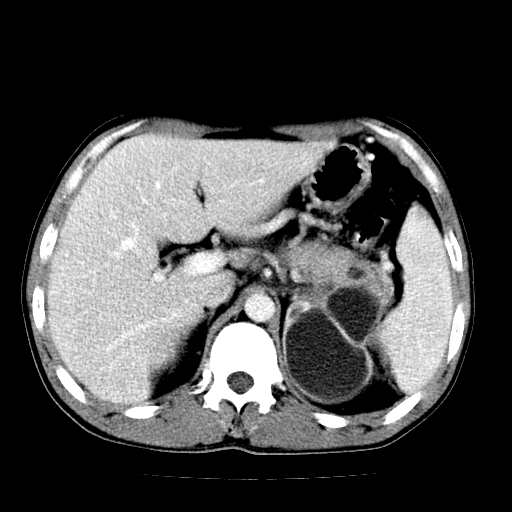

以下是引用天南地北在2007-4-30 13:36:00的发言:[br]支持慢性胰腺炎伴有假性囊肿

以下是引用andymaomao在2007-4-30 14:28:00的发言:[br]支持:1.慢性胰腺炎并假性囊肿形成可能;[br] 2.左肾形态稍增大,旋转不良。